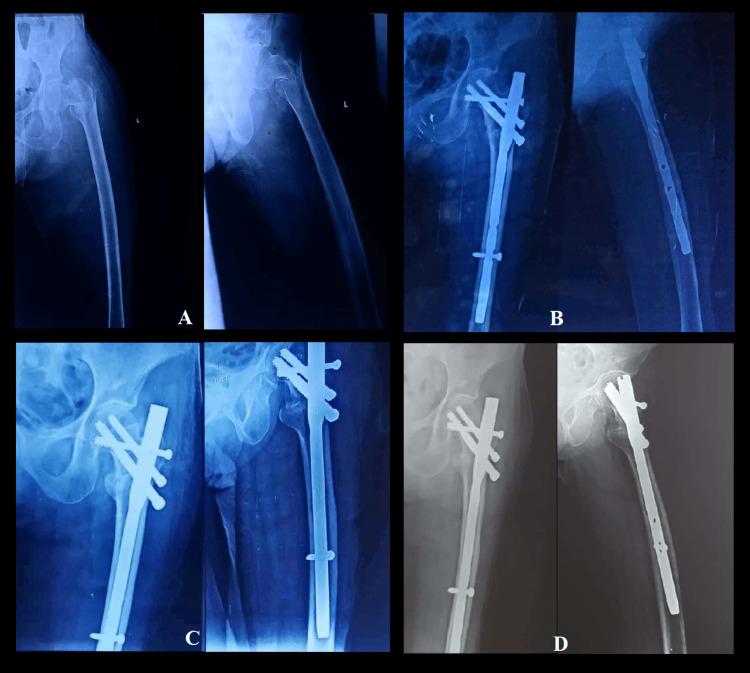

Introduction The proximal femoral nail (PFN) is a widely accepted fixation method for the management of unstable intertrochanteric fractures. Reconstructing the lateral trochanteric wall and ensuring the stability of the trochanteric fragments are considered to be essential for enhancing the prognosis of unstable intertrochanteric fractures. The aim of this study is to evaluate and compare the results of the management of unstable intertrochanteric fracture of the femur using PFN and the screw-augmented PFN (aPFN). Methods This prospective comparative study was undertaken from January 2020 to July 2021 and included 60 patients presenting with unstable intertrochanteric fractures (AO/OTA type 31-A2.2 and 31-A2.3) at a tertiary care teaching institute in northern India. The enrolled patients were randomly divided into two groups (group 1 and group 2) and were managed with screw-augmented PFN and PFN, respectively. Functional outcome was evaluated using the Salvati and Wilson score at the 12-month follow-up. SPSS version 24.0 (IBM Corp., Armonk, NY, USA) was used for statistical analysis. A p-value less than 0.05 was regarded as significant. Results The average time to union of the fractures in group 1 was 12.66 ± 1.68 weeks, while it was 13.47 ± 1.47 weeks in group 2 (p = 0.055). At the 12-month follow-up, the average functional outcome, as evaluated by Salvati and Wilson score, was 34 ± 2.40 in group 1, whereas it was 31.58 ± 4.4 in group 2; and the difference was observed to be statistically significant (p = 0.011). Group 1 had 28 patients (93.33%) with excellent to good results, while group 2 had 25 patients (83.33%) with excellent to good results. One patient in group 1 and five patients in group 2 had poor outcomes at the 12-month follow-up. Conclusion Screw-augmented PFN has better functional outcomes as compared to PFN alone for the management of unstable intertrochanteric fractures. Hence, in our opinion, screw augmentation of PFN may be the better fixation technique for most unstable intertrochanteric femur fractures.

引言 股骨近端髓内钉(PFN)是治疗不稳定型股骨转子间骨折广泛采用的固定方法。重建股骨外侧壁并确保转子间骨折块的稳定性被认为是改善不稳定型股骨转子间骨折预后的关键。本研究旨在评估和比较使用PFN与螺钉增强型PFN(aPFN)治疗不稳定型股骨转子间骨折的效果。方法 本前瞻性对照研究于2020年1月至2021年7月进行,纳入了印度北部一家三级医疗教学机构的60例不稳定型股骨转子间骨折患者(AO/OTA 31-A2.2和31-A2.3型)。将入选患者随机分为两组(第1组和第2组),分别采用螺钉增强型PFN和PFN进行治疗。在12个月随访时,采用Salvati和Wilson评分评估功能结果。使用SPSS 24.0版(美国纽约州阿蒙克市IBM公司)进行统计分析。p值小于0.05被视为具有统计学意义。结果 第1组骨折平均愈合时间为12.66±1.68周,而第2组为13.47±1.47周(p = 0.055)。在12个月随访时,根据Salvati和Wilson评分评估,第1组平均功能结果为34±2.40,而第2组为31.58±4.4;差异具有统计学意义(p = 0.011)。第1组有28例患者(93.33%)结果为优至良,而第2组有25例患者(83.33%)结果为优至良。在12个月随访时,第1组有1例患者、第2组有5例患者结果较差。结论 对于不稳定型股骨转子间骨折的治疗,螺钉增强型PFN比单纯PFN具有更好的功能结果。因此,我们认为,对于大多数不稳定型股骨转子间骨折,PFN的螺钉增强可能是更好的固定技术。